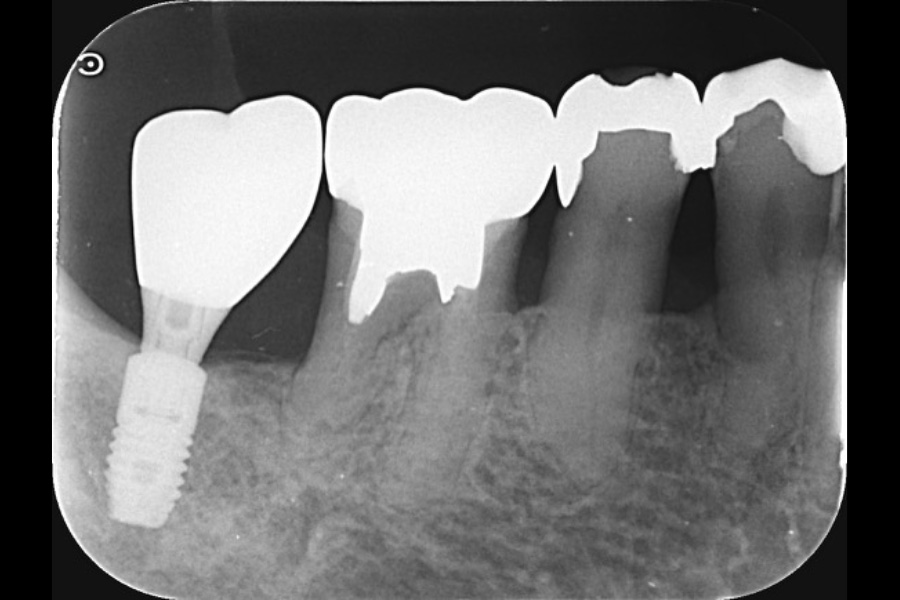

右下奥歯の歯ぐきから出血する

【歯周組織再生療法】

- 主訴

- 右下奥歯の歯ぐきから出血する

- 治療内容

- 右下6遠心に垂直性骨吸収が認められたためエムドゲインと骨補填材を用いて歯周組織再生療法を行った